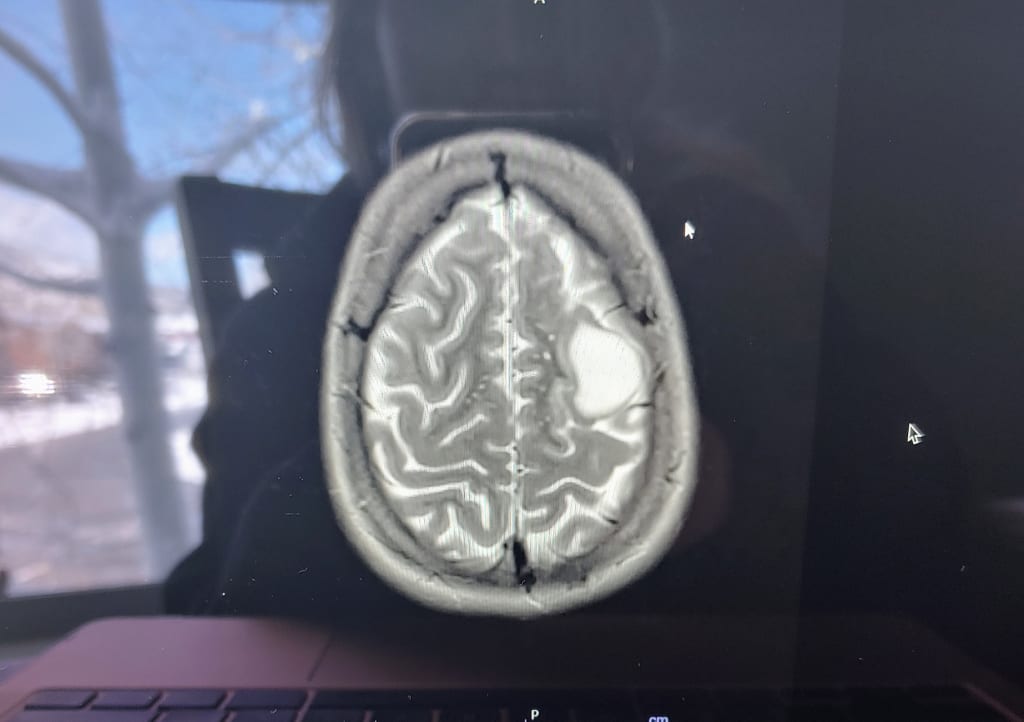

I met Dr. Hudson on a zoom call with my mom. He showed us the clearly misplaced bright white mass on my recent MRI and informed us there was, in fact, a demon marshmallow growing in my brain. I was stoked; I knew what was wrong with me. I identified as a very happy person and had a record low amount of stress in my life, but my panic attacks had increased from monthly to sometimes multiple times a day. I had a panic attack at work and quit my job. I called into another job crying and hyperventilating on the bathroom floor, unable to find a reason to be so upset. I got unreasonably angry at strangers and at my friends. I did yoga and breathing exercises and cold exposure and cross country skied with my friends: nothing helped. I started to spend as much time running in the mountains as I could because it's always helped me get my head on straight. Not only was my head not on straight, it was performing an exorcist-style spin. I felt absolutely possessed, and I was ready for my lobotomy.

The extra fun part was that the tumor was close to the speech-area of my brain, so he said I may have to be awake so that I can talk to them so they know they aren’t damaging my speech. I panicked so often over nothing, but with information like this, I felt calm. Luckily, a functional MRI showed they had a little space between the tumor and the area of my brain that lit up when I spoke, so I got to be knocked out for surgery.